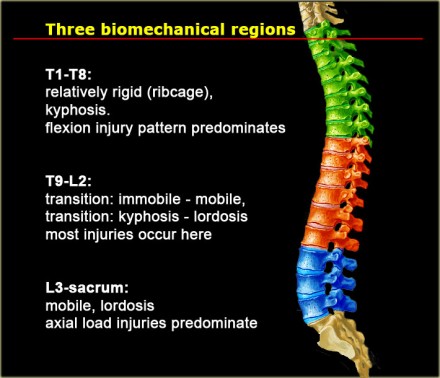

Biomechanics

In the thoracolumbar spine there are three biomechanical regions.

The upper thoracic region (T1-T8) is rigid due to the ribcage which provides stability.

The transition zone T9-L2 is the transition between the rigid and

kyphotic upper thoracic part and the flexible lordotic lumbar spine.

This is where most injuries occur.

Finally we have the L3-Sacrum zone which is flexible and this is the region where axial loading injuries occur.

In the upper thoracic spine the center of gravity is anterior to the spine.

Axial loading will result in compressive forces anteriorly and tensile forces posteriorly.

This will result in flexion-type of injuries.

In the lumbar spine due to the lordosis, the center of gravity is posteriorly.

Flexion type of injuries will straigthen the lumbar spine and result in axial loading.

In this area we will see many burstfractures.